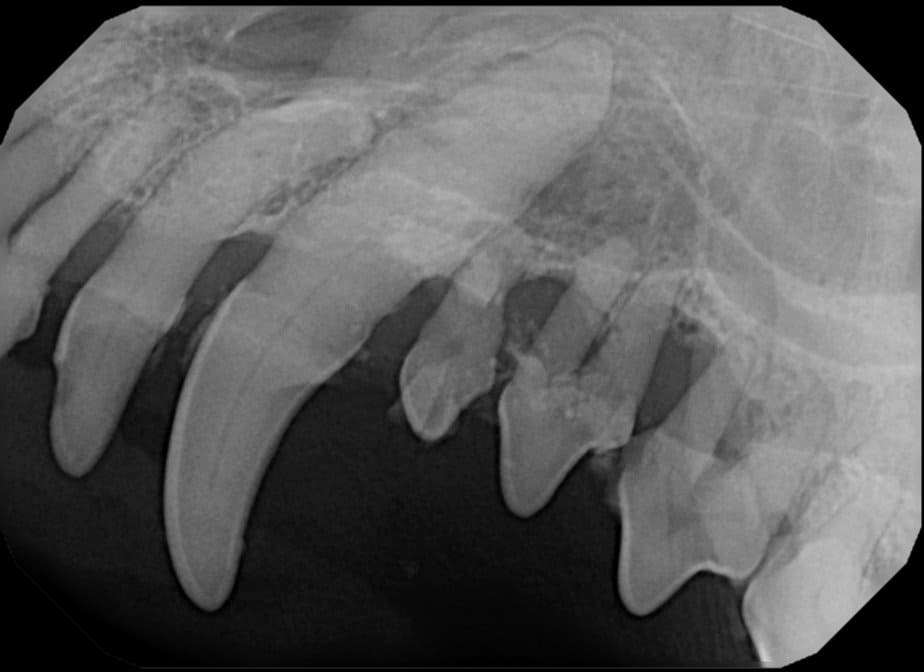

The Center now provides advanced imaging via cone beam CT. Cone beam CT is excellent for visualization of bony structures of the skull, nasal cavity, teeth, and ears. Cone beam CT is especially helpful for diagnosing dental disease and evaluation of jaw fractures. It can also be useful for evaluating the sinuses and tympanic bulla. Cone beam CT can be used in conjunction with nasal biopsy and culture to evaluate nasal discharge whether chronic or acute.

Periodontal disease is extremely common in dogs and cats. Over 80% of dogs and cats over two years of age have some degree of periodontal disease. Periodontal disease is best prevented by yearly professional dental cleanings starting at two years of age and at home brushing at least three times weekly. Brushing should begin at a very early age to allow your new pet to get used to regular brushing. In severe cases of infection or periodontal disease, the teeth may need to be surgically extracted. Extractions should always involve x-rays of the tooth first, as many teeth have multiple roots or may be diseased below where the eye can see. Extracting larger teeth in animals requires oral surgery, equivalent to removing wisdom teeth in people. It is vital that all of the tooth and roots be removed for the periodontal infection to resolve. In cases of important teeth with mild to moderate periodontal disease, multiple periodontal treatments can be offered to help save these teeth.

Tooth resorption is a disease process where the body begins to break down the adult tooth. It is widely known to occur in cats but can also occur in dogs. In cats these lesions are thought to be inflammatory, while in dogs they can be more of a replacement resorption process. These lesions can be very painful and should be treated, generally with extraction depending on the type of resorption that is occurring. The disease can be progressive and affect many teeth over several years. It is important to have regular checkups and yearly dental cleanings to monitor for these lesions.